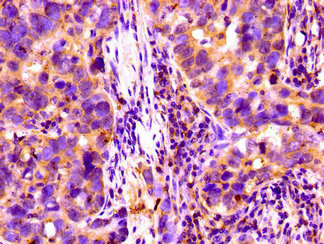

Immunohistochemistry of paraffin-embedded human pancreatic cancer using CSB-PA005279LA01HU at dilution of 1:100